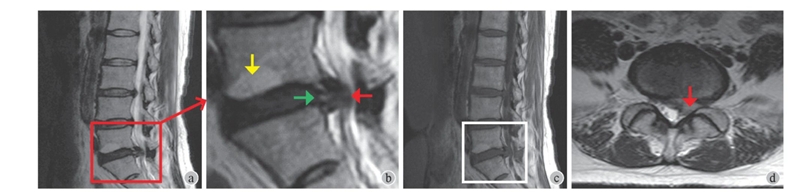

MRI (图1):L5~S1椎间盘向左后方脱出,压迫左侧S1神经根;此外矢状位MRI 显示L5椎体下终板Mordic改变,L5~S1椎间盘后缘有高信号区(high intensity zone,HIZ)。

图1术前腰椎MRI

a~b:T2加权矢状位MRI显示L5~S1椎间盘脱出 (红箭头)、椎间盘后缘HIZ (绿箭头),L5椎体下终板炎 (黄箭头);c:T1加权矢状位MRI显示L5~S1椎间盘脱出、L5椎体下终板Mordic II型改变;d:T2加权轴位MRI显示L5~S1椎间盘脱出